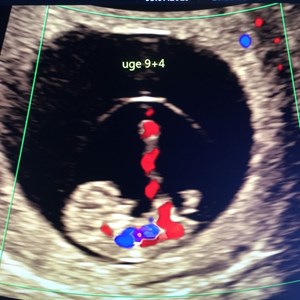

Billeder fra livets begyndelse ✨ Scanning i 9. graviditetsuge. Billede i 2D og 3D. Læg mæ...